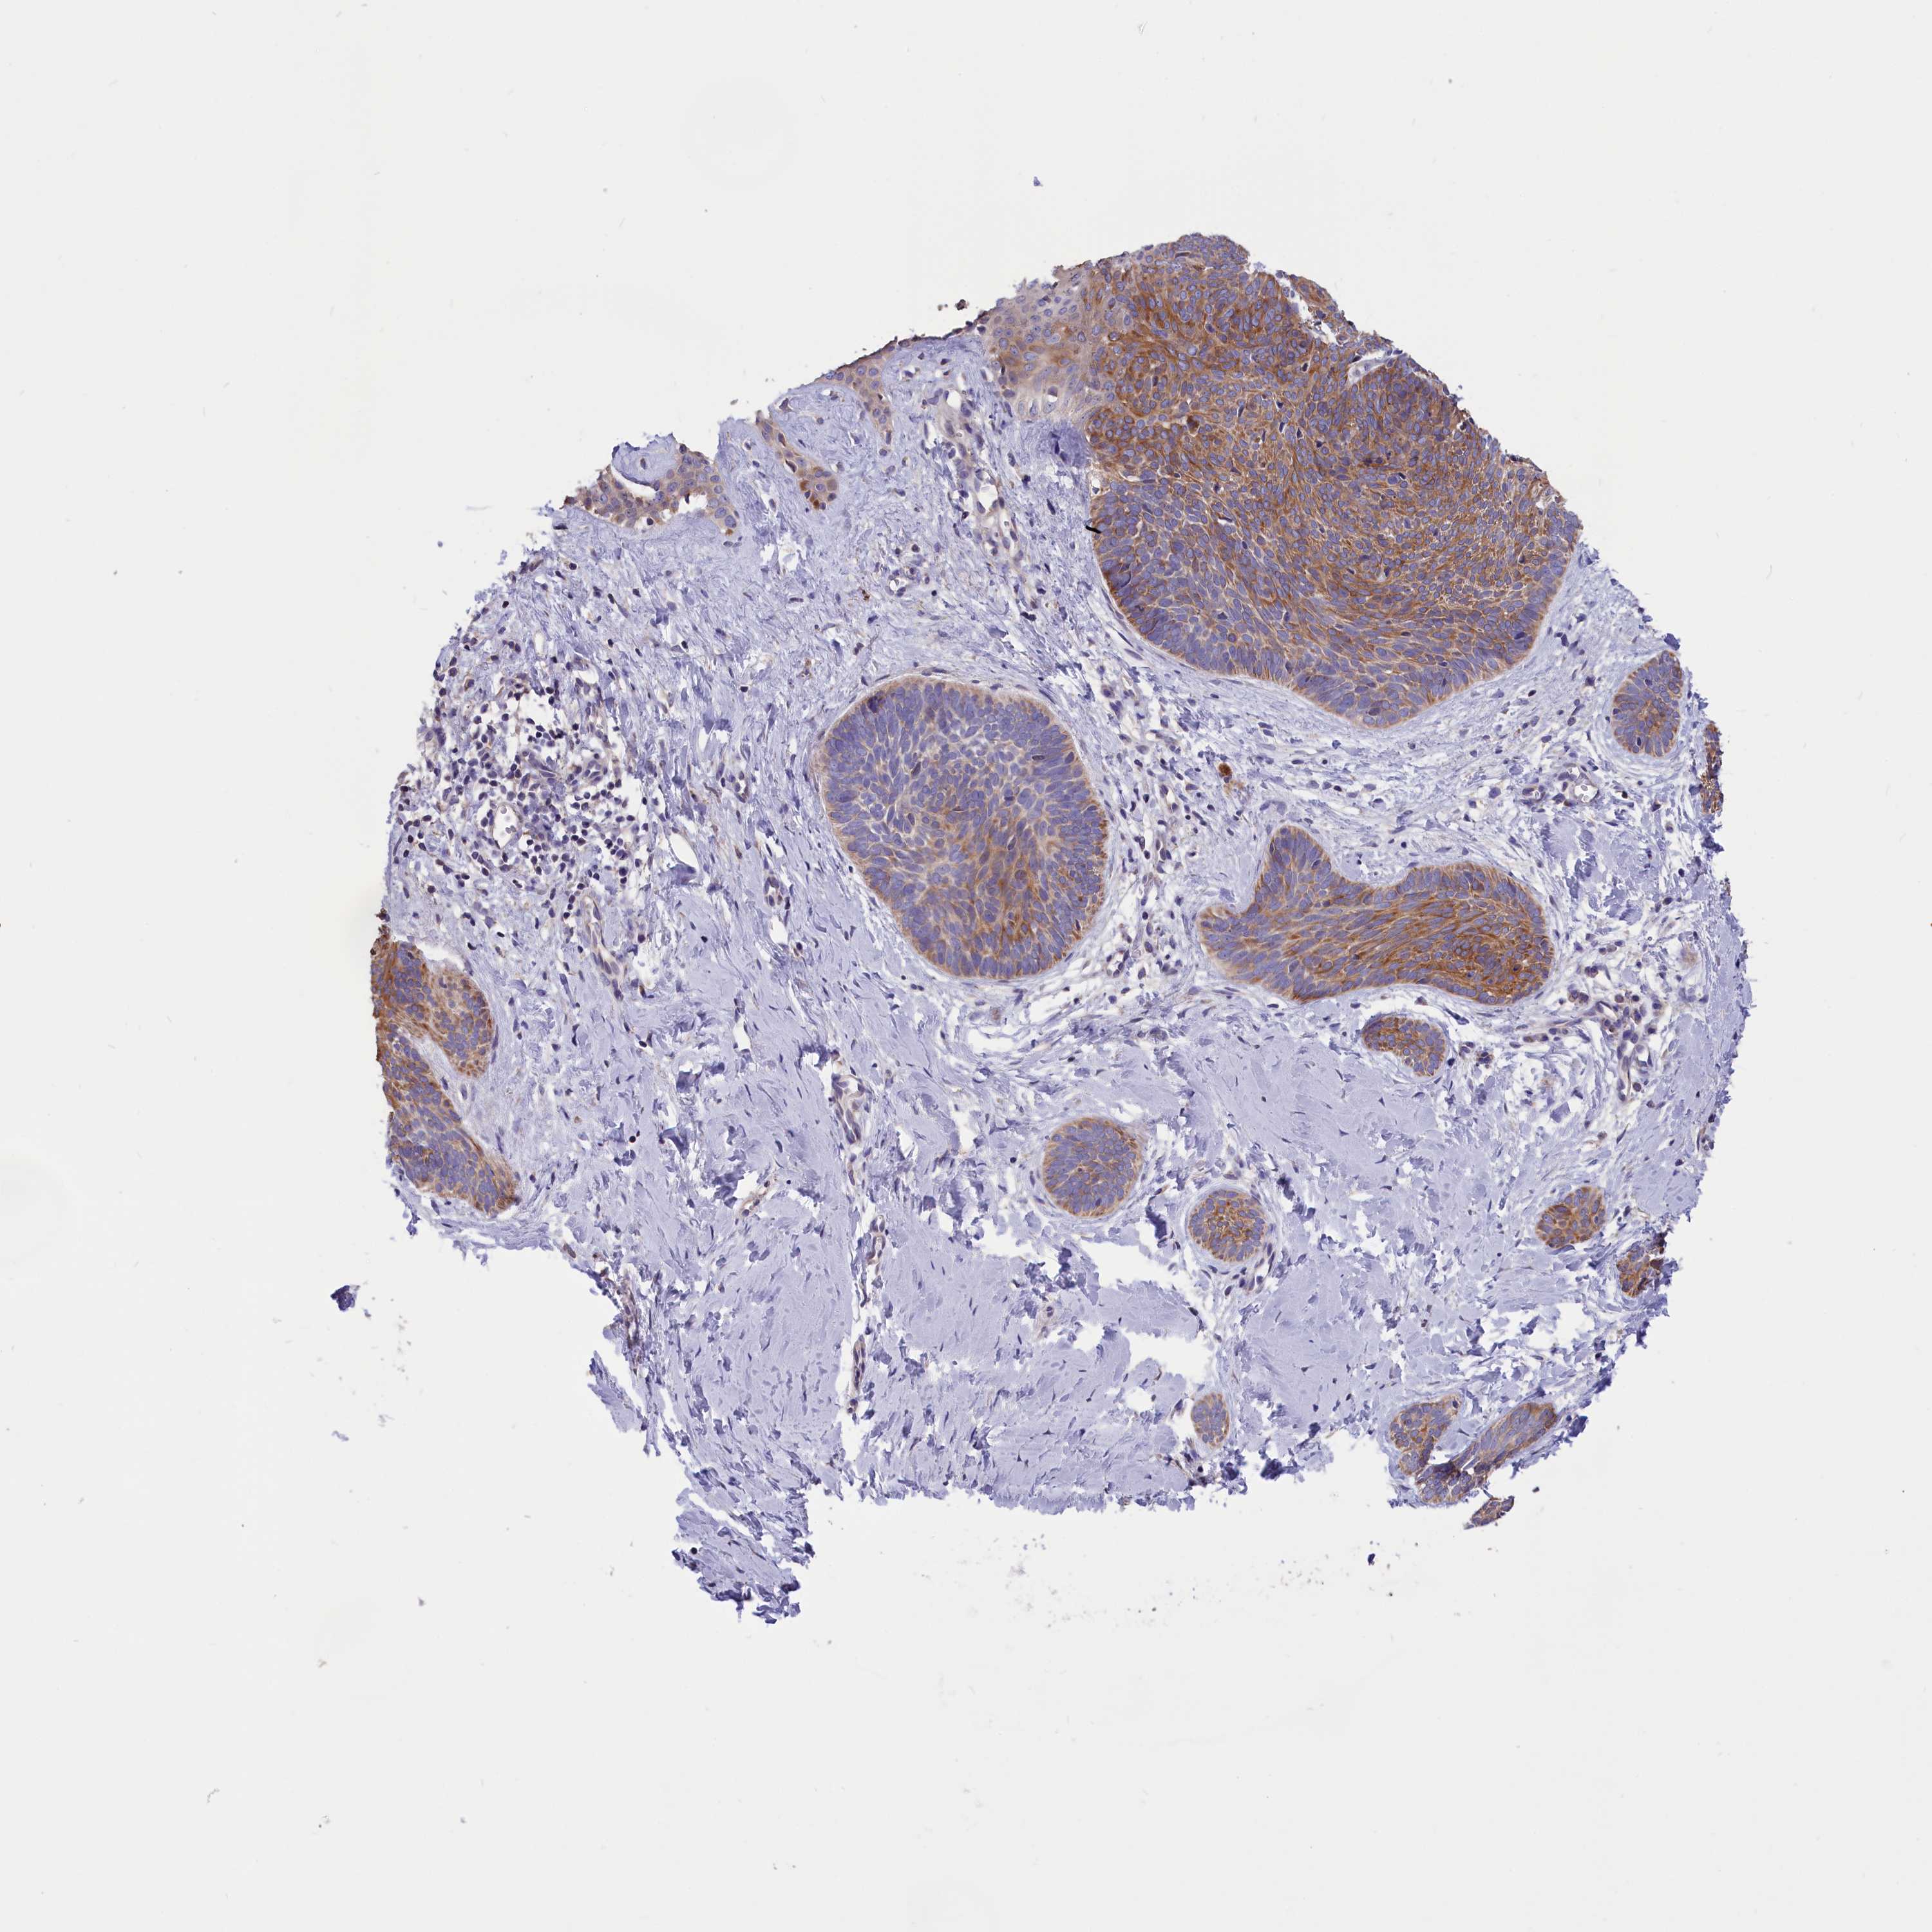

SKIN CANCER - Protein expressioni

A mouse-over function shows sample information and annotation data. Click on an image to view it in a full screen mode. Samples can be filtered based on level of antibody staining by selecting one or several of the following categories: high, medium, low and not detected. The assay and annotation is described here.

Each image is clickable and will lead to virtual microscopy that enables deeper exploration of all samples and also displays staining intensity scores, fraction scores and subcellular localization as well as patient and tissue information for each sample.

Antibody HPA041622

Staining

High

Intensity

Strong

Quantity

>75%

Location

Cytoplasmic/membranous

Basal cell carcinoma

Squamous cell carcinoma, NOS